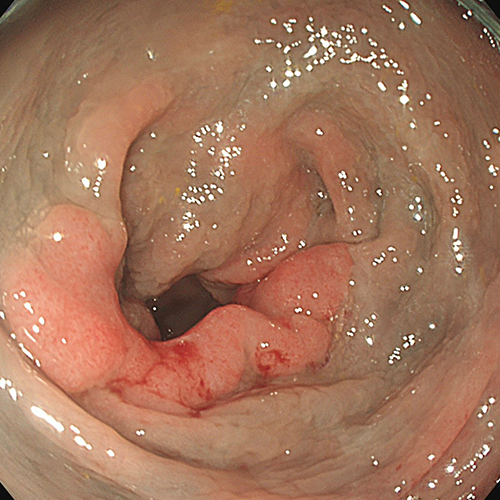

The lesion was located in a challenging position in the Splenic flexure of the left colic of the colon.

The lesion was non-granular laterally spreading tumour (LST-NG) and 40x20mm is size.